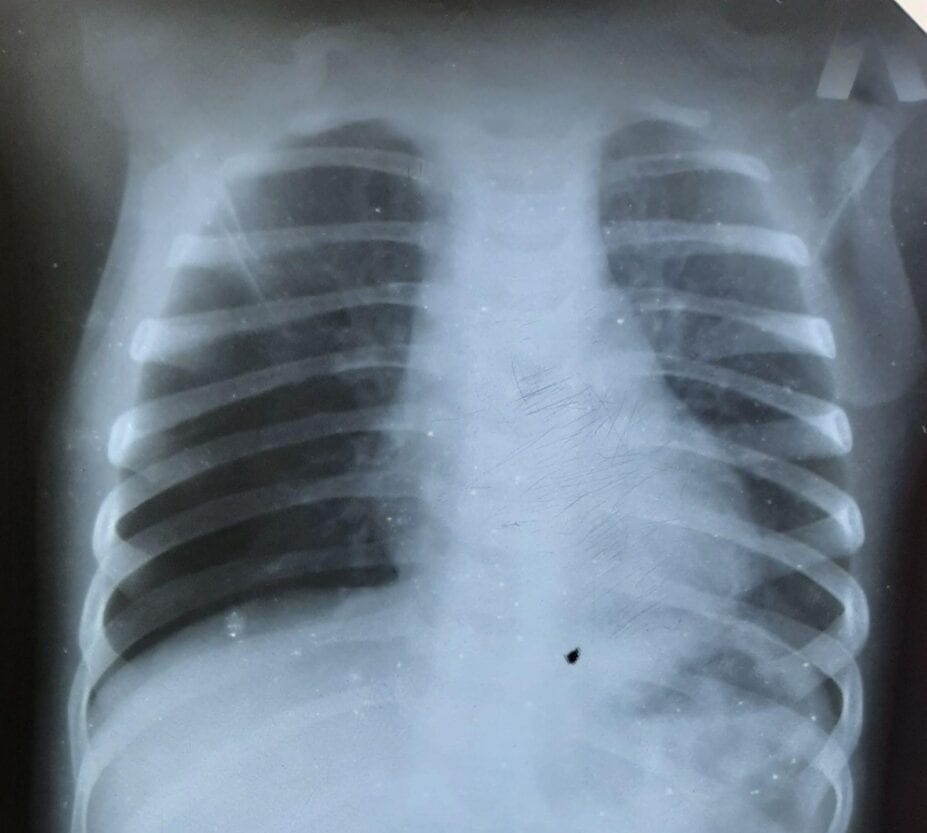

На основании данных проведенных обследований врачи заподозрили, что в бронхах девочки находиться инородное тело.

В связи с этим ребенку провели лечебно-диагностическую бронхоскопию. С правого главного бронха было удалено инородное тело, фрагмент грецкого ореха.